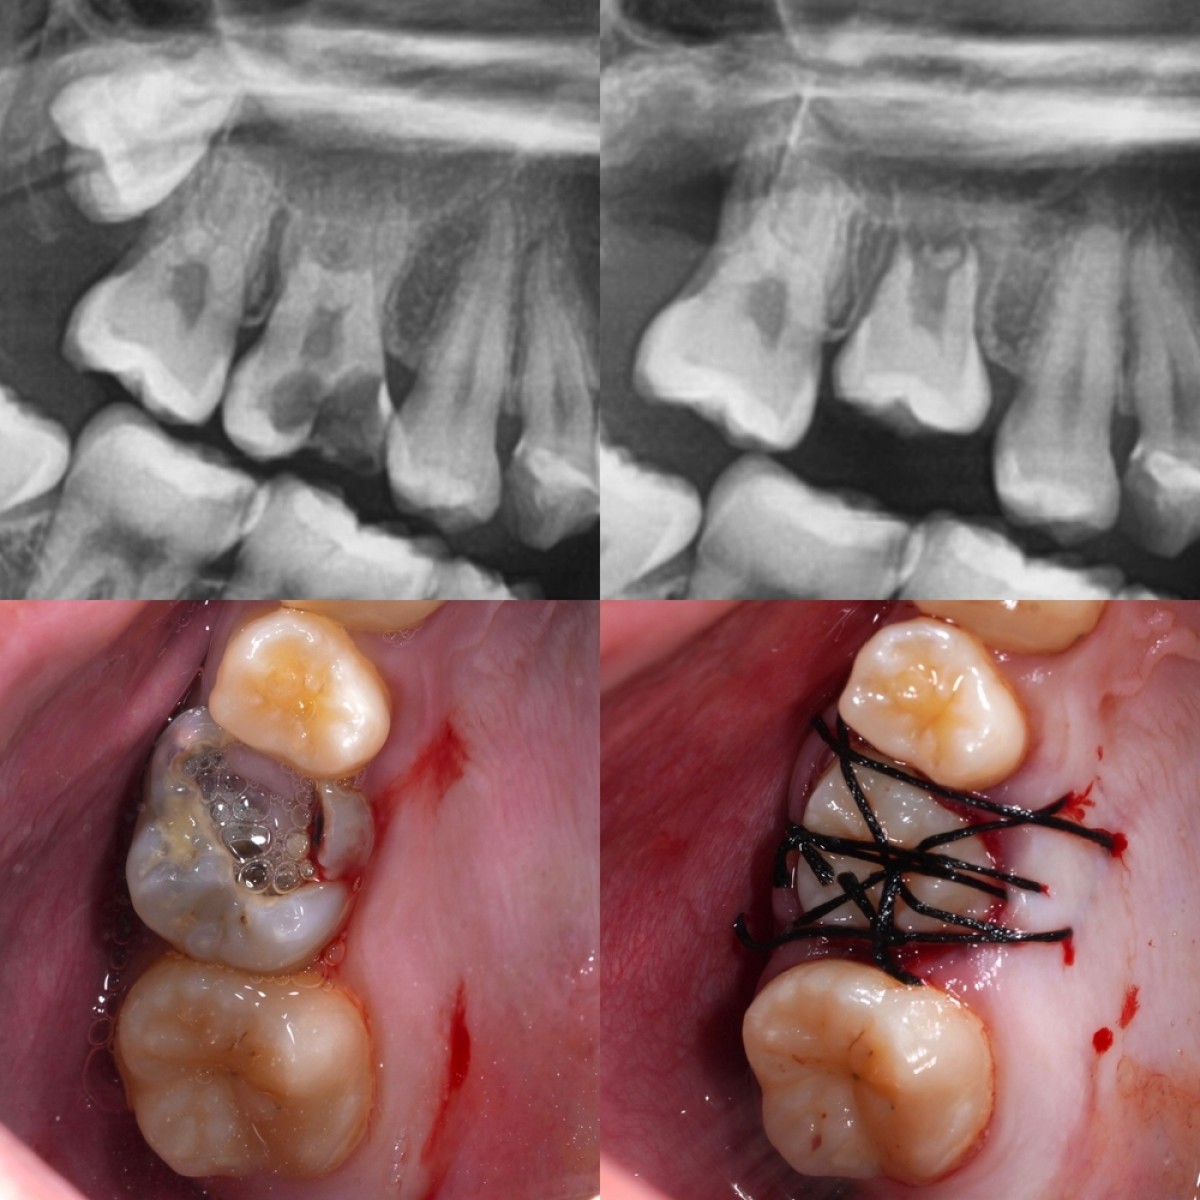

無菌的処置とスピーディーな手術

五反田の歯医者、ツツミ歯科クリニックの自家歯牙移植

歯根膜は乾燥や細菌に非常に弱いため、抜いてから植えるまでの時間は短ければ短いほど成功率が上がります。

30年の外科経験を持つ院長が、手際よく、かつ丁寧に手術を行います。

移植後の「根管治療」と「固定」

移植した歯が周囲の組織と結合するまで、しっかりと固定を行います。

また、神経の処置が必要な場合は、当院が得意とする精密根管治療を行うことで、移植した歯を長期的に安定させます。